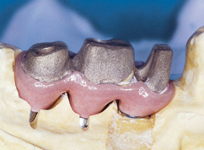

Protetické řešení může být pomocí můstku, který je kotvený na implantátech nebo pomocí jednotlivých korunek na implantátech.

V zásadě je možné do těchto můstků zařadit i přirozené zuby, zejména pokud je potřeba tyto zuby ošetřit proteticky

- korunkami. Korunky nebo můstky mohou být na implantáty nacementovány nebo přišroubovány.